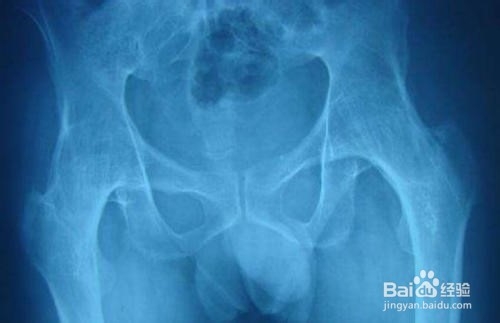

2、脊柱拉伸运动是AS运动锻炼的核心,包括脊柱在冠状位(左右)、矢状位(前后)以及旋转性运动。拉伸运动可以改善脊柱的活动程度,延缓脊柱发生功能受损(弯腰、驼背、活动受限)的时间。

5、AS患者进展,往往出现弯腰驼背等现象,随之而来的是平衡力的下降,行走容易欠稳。这时候,我们需要进行平衡训练、肌力训练,增加下肢、中轴肌肉力量,维持躯体稳定,提高肌体平衡能力,降低摔倒发生的风险。